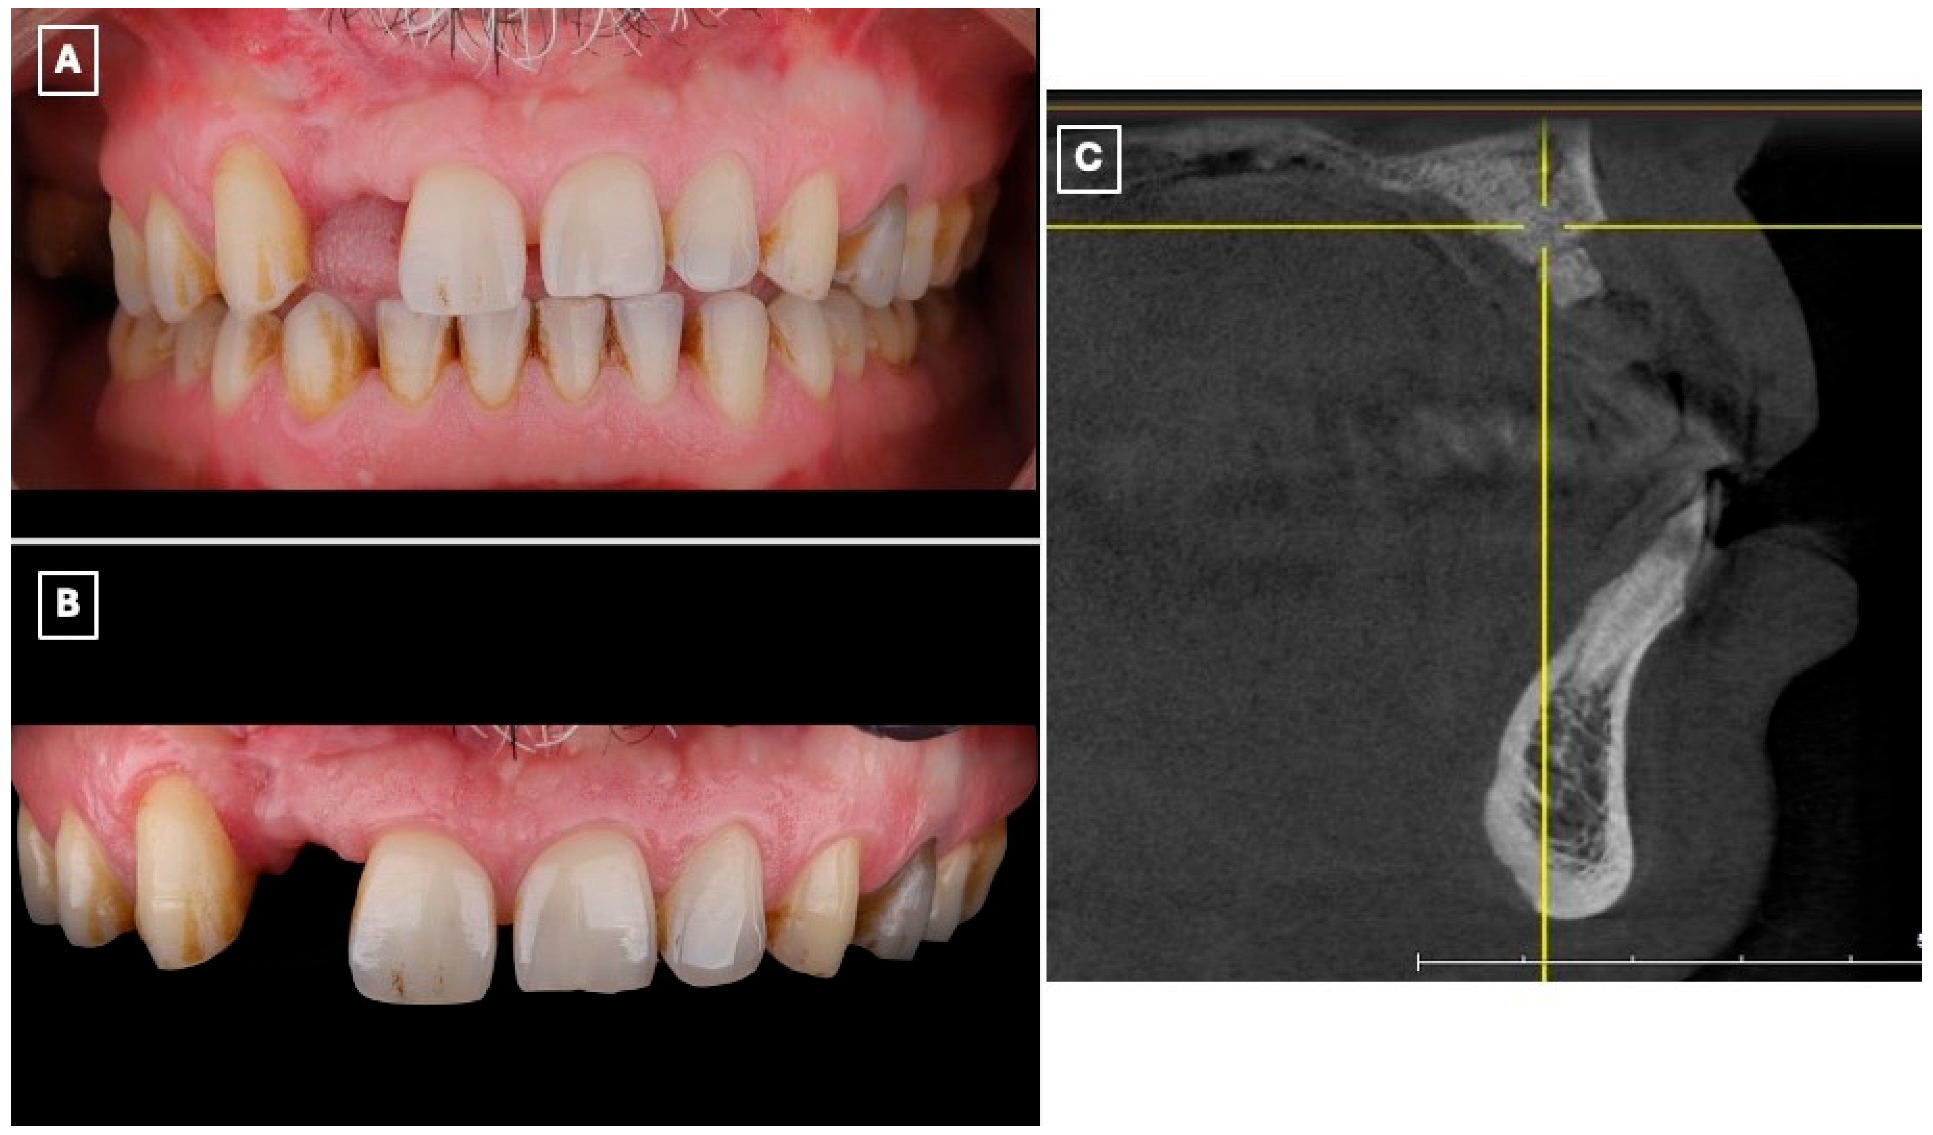

A 45-year-old male presented to the Prosthodontics Clinic at King Abdulaziz Medical City, Ministry of National Guard, Jeddah, Saudi Arabia, with a missing maxillary right lateral incisor (#12) and requested esthetic rehabilitation (Figure 1A,B). His chief complaint was: “I want my smile improved and the missing tooth replaced with a natural-looking option.” The patient reported no relevant medical conditions, and both medical and family histories were noncontributory.

Figure 1.

Preoperative clinical and radiographic assessment of the maxillary anterior region supporting treatment selection. (A) Frontal intraoral view demonstrating the missing maxillary right lateral incisor (#12), associated asymmetry of the anterior smile line, and localized esthetic disharmony within the maxillary anterior segment. (B) Closer intraoral view highlighting the edentulous space, favorable gingival architecture, and intact adjacent enamel surfaces, which are prerequisites for predictable enamel-bonded adhesive restorations. (C) Sagittal cone-beam computed tomography (CBCT) cross-sectional image of the lateral incisor region demonstrating limited residual alveolar ridge width and altered ridge contour following previous augmentation procedures. These findings, in conjunction with prior surgical outcomes and patient preference to avoid further intervention, supported the exclusion of implant therapy and the selection of a minimally invasive, non-surgical adhesive prosthodontic approach.

The patient had previously undergone multiple bone augmentation procedures in the periodontics department; however, despite these interventions, the residual alveolar ridge volume in the maxillary right lateral incisor region remained insufficient for predictable implant placement. This assessment was based on prior surgical outcomes, clinical ridge morphology, and interdisciplinary evaluation. Preoperative cone-beam computed tomography (CBCT) imaging (Figure 1C) demonstrated limited bucco-lingual ridge width and an unfavorable ridge contour at the lateral incisor site, further supporting the decision to exclude implant therapy.